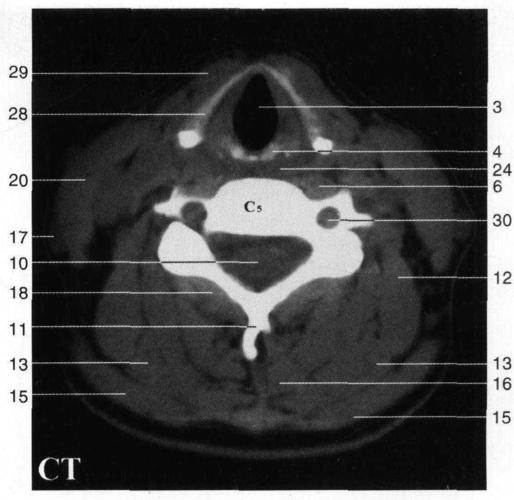

甲状软骨解剖图ct,甲状软骨解剖图

甲状软骨右板right lamina of thyroid cartilage 29.